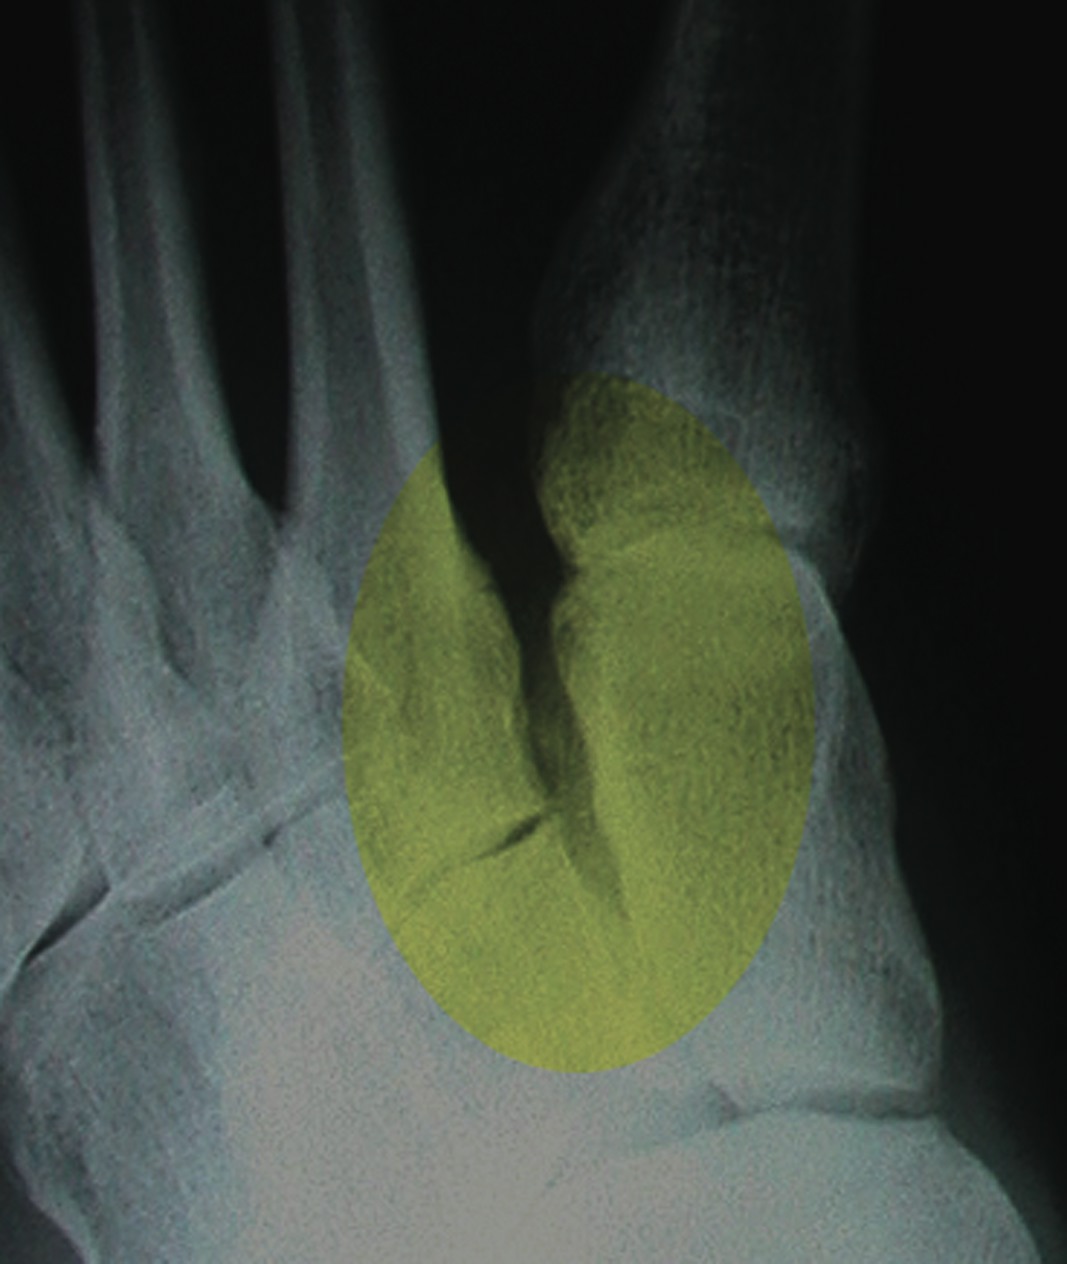

Which Medial Column Joint Is Responsible For Hypermobility?

Two separate cadaveric studies have attempted to determine the contribution of medial column joints to total mobility. Roling and colleagues performed selective arthrodeses in a cadaveric open kinetic chain study on six specimens.23 The cited contributions are as follows: talonavicular joint (9 percent), naviculocuneiform joint (50 percent) and first MCJ (41 percent). Faber, et. al., performed a similar cadaveric study in hallux valgus feet and demonstrated that the first MCJ contributed 57 percent, the talonavicular joint contributed 8 percent and the naviculocuneiform joint contributed 35 percent of medial column motion.24 Both cadaveric studies suggest the first MCJ is a large contributor to medial column mobility. In the presence of hypermobility, it may be unclear which of the medial joints are specifically responsible for the excessive motion from the clinical exam alone. In some cases, one may see the gross motion on the dorsal aspect of the first MCJ when testing sagittal first ray motion. McInnes and Bouche perform an isolated dorsal drawer (translation only) of the first MCJ and consider excessive motion indicative of the first MCJ instability.14 The radiographs often offer clues to which medial column joint is involved. Clinicians can discern obvious sagittal plane collapse of the first MCJ or naviculocuneiform joint. Drawing Meary’s angle may identify subtle collapse. In some cases, one may identify slight widening of the plantar aspect of the first MCJ. The presence of medial cuneiform obliquity and metatarsus primus adductus suggests the first MCJ as a prime contributor to medial column mobility. Diastasis of the first intermetatarsocuneiform area suggests more proximal hypermobility. I believe this widening may represent attenuation of Lisfranc’s ligament and may indicate transverse plane instability. In some cases, more proximal instability from the first intercuneiform or naviculocuneiform joint may contribute to the hypermobile segment. This may result in persistent transfer metatarsalgia or lesser metatarsal stress fractures after a Lapidus. Unappreciated hypermobility, especially in the transverse plane, is the cause of bunion recurrence after an isolated first MCJ arthrodesis for hallux valgus.